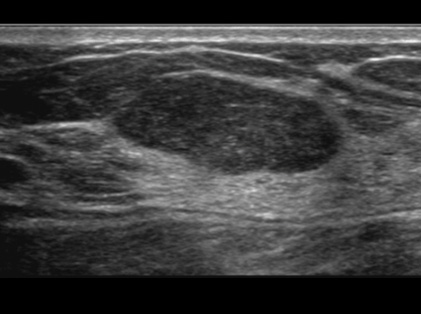

◆ 결절의 특징

1) 모양 : 불규칙하거나 찌그러진 모양의 결절은 암일 가능성이 높습니다.

2) 경계 : 경계가 명확하지 않고 주변 조직과 침범하는 형태의 결절은 암일 가능성이 높습니다.

3) 크기: 일반적으로 2cm 이상의 결절은 암일 가능성이 높습니다.

4) 성장속도: 빠르게 성장하는 결절은 암일 가능성이 높습니다.

ㆍ유방 초음파 : 초음파를 이용하여 유방의 내부를 관찰하는 검사입니다. 유방을 압박하지 않고 검사할 수 있으며 통증이 없습니다. 또한, 유방의 모든 조직을 관찰할 수 있어 유방암의 조기 발견에 효과적입니다.